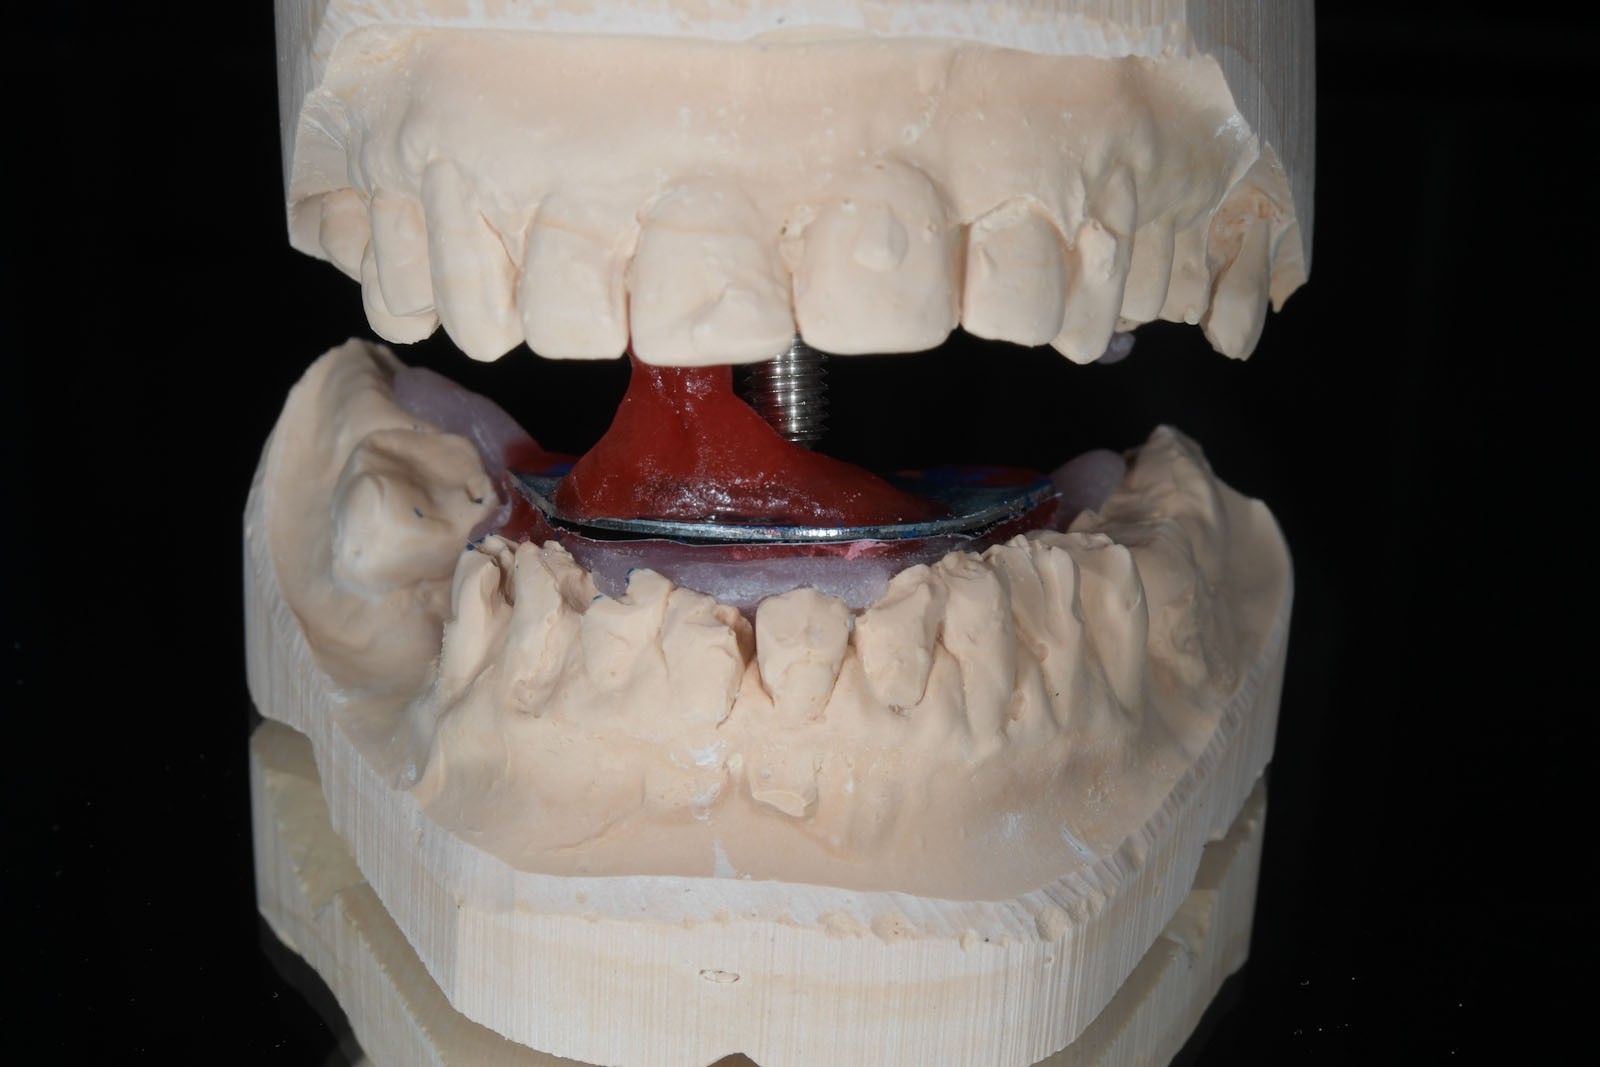

W celu ustalenia wzajemnej relacji żuchwy i szczęki Gerber poleca rejestrację z użyciem centralnego sztyftu podpierającego, który zapewnia równomierne obciążenie podłoża protetycznego i stawów skroniowo-żuchwowych, a także ułatwia centralne ułożenie głów stawowych dzięki trójpunktowemu podparciu żuchwy w stosunku do czaszki.

W pierwszym etapie wykonuje się modele robocze, które są montowane w opracowanym przez prof. Gerbera artykulatorze. Tak zwany condylator pozwala na symulację trójwymiarowych ruchów głów żuchwy. Pozwala na zweryfikowanie poprawności relacji pomiędzy łukiem zębowym górnym a dolnym. Po dokładnym zbadaniu funkcji i morfologii stawu sż, wykonaniu pomiarów oraz ocenie stanu zdrowia zębów zostaje opracowany indywidualny plan leczenia zgodny z uwarunkowaniami pacjenta.

Dzięki zastosowaniu łuku twarzowego możliwy jest pomiar kątów nachylenia torów przesuwania głów żuchwy. Pozwala to na zamontowanie modeli gipsowych w stosunku do stawów skroniowo-żuchwowych i płaszczyzny Campera (linii uszno-nosowej) orientacyjnej w widoku z profilu. Ma to na celu odtworzenie prawidłowej okluzji, czyli odpowiedniej pozycji stykania się zębów górnych z dolnymi.